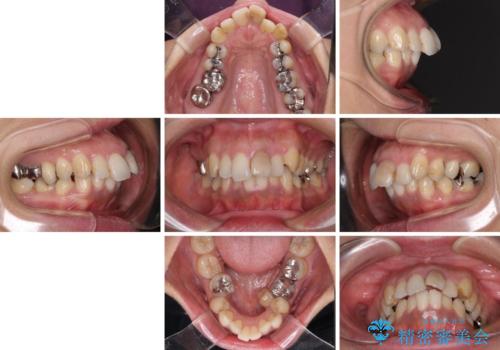

- 歯列全体が内側に倒れ込んでいることと、口元の突出感を気にして来院された患者様です。

上下ともに歯列が狭窄しており、前方に突出している状態でした。

歯が重なるような叢生も認められたため、上下左右の第一小臼歯4本を抜歯して、口元が引っ込むように治療を行うこととしました。

口元を引っ込めることができたため、口を閉じるときに力が入っていて皺のよっていた顎先も、スムーズに閉じられるようになったことで力がかからなくなりました。

変色して気になっていた前歯も、オールセラミッククラウンで自然な色合いにすることができました。